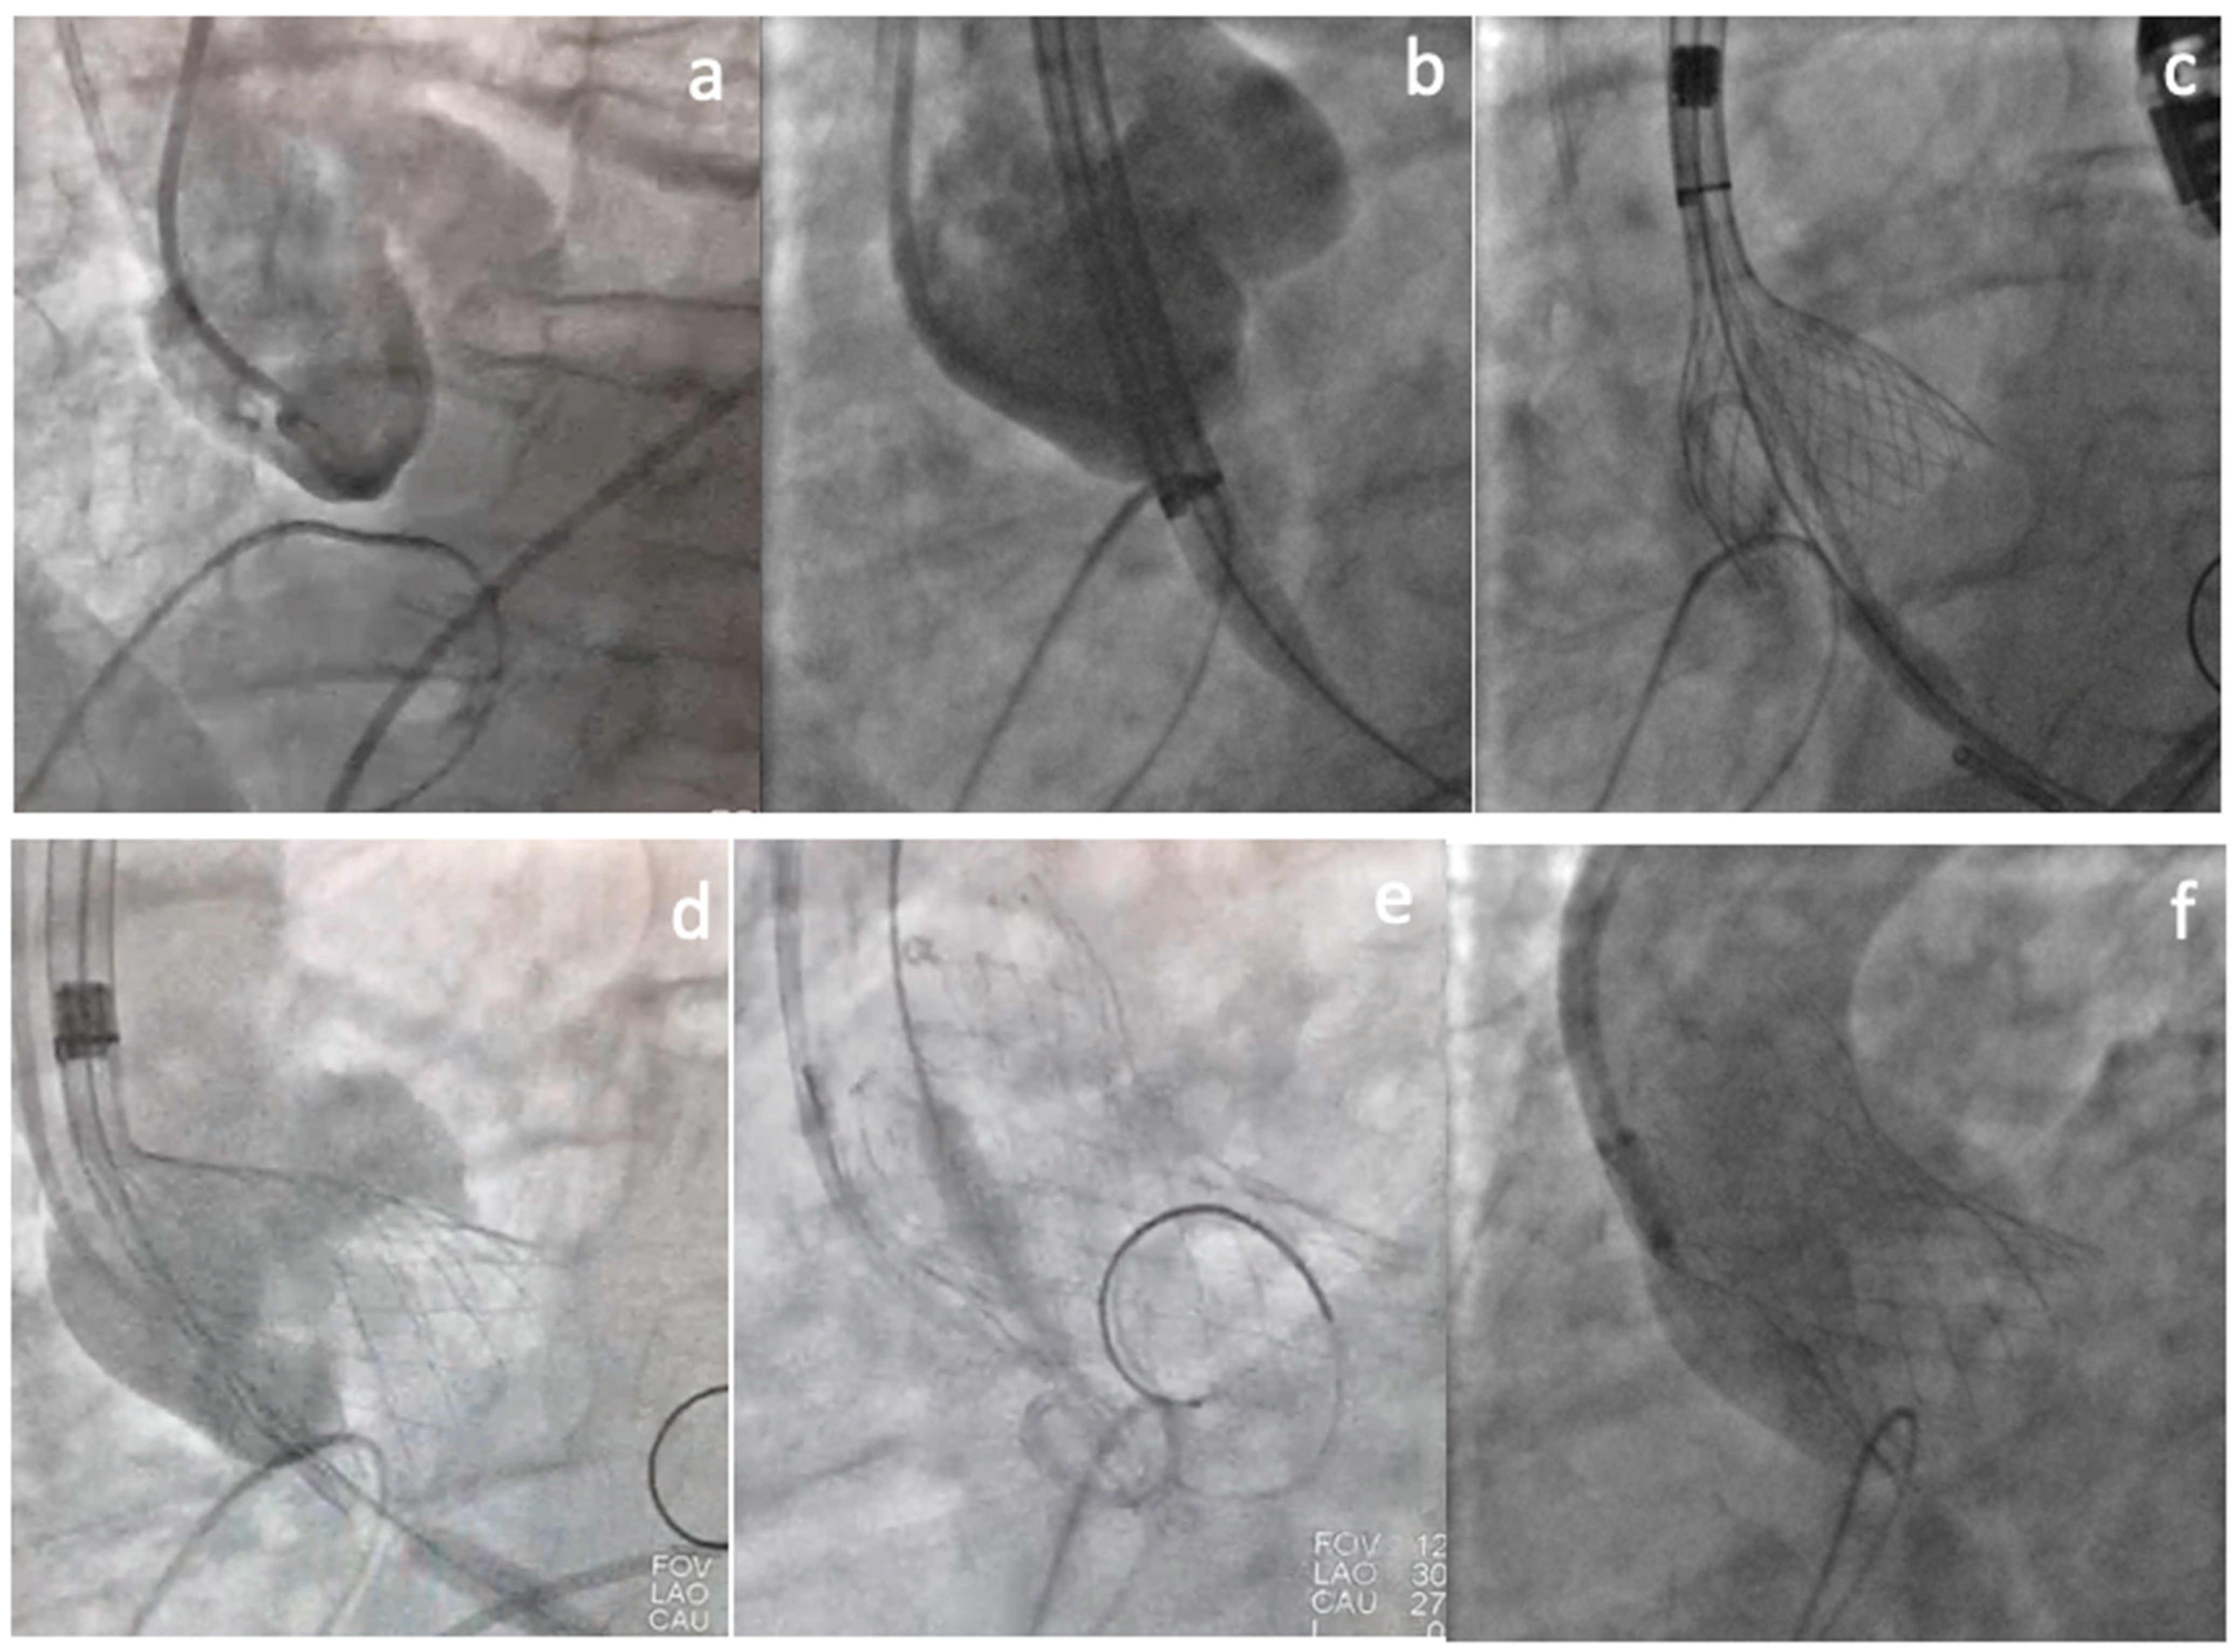

2. Clinical Vignette